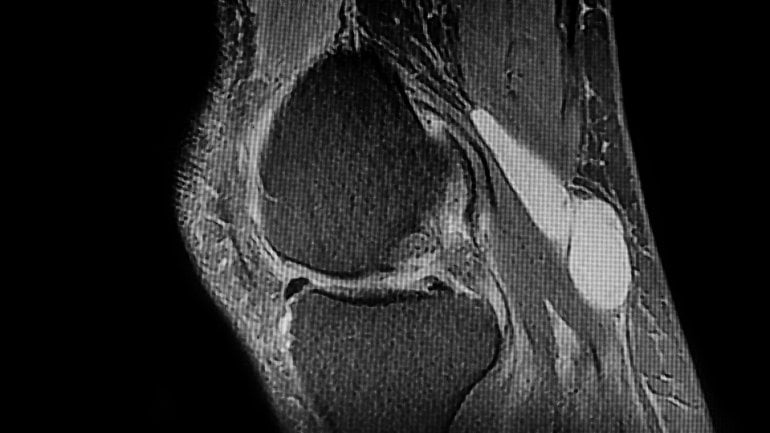

Schmerzen in der Kniekehle: Was kann es sein?